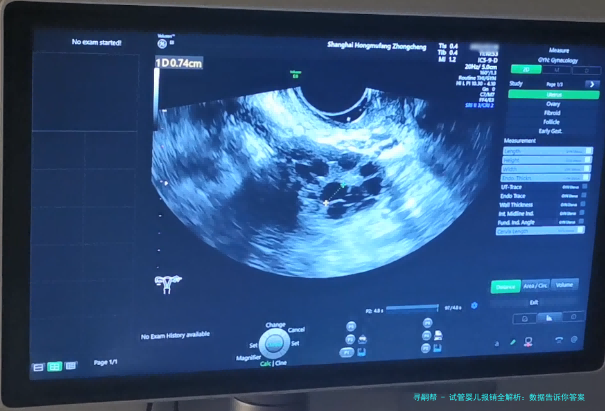

试管婴儿,医学上称为体外受精-胚胎移植,说白了就是把卵子和精子在实验室里结合,再放回妈妈子宫里。这技术在中国已经挺成熟了,据国家卫健委的数据,2020年中国试管婴儿周期数超过100万例,比2015年增长了近50%,这背后反映出需求的激增和技术的普及。不过,费用问题一直是拦路虎,普通家庭得攒好一阵子钱才能负担得起。